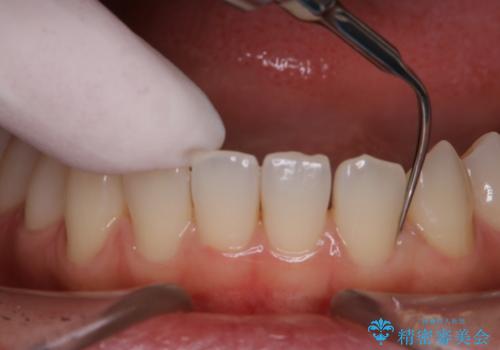

- 忙しくて、しばらくクリーニングをしていないため、全体的にしっかりとクリーニングしてほしいとのことでした。PMTC60分コースを行いました。

プラークやバイオフィルムといった細菌などを放置すると歯石となります。歯石になってしまうと歯磨きでは取り除くことができないため、歯科医院にて専門的な機械や材料を使用してクリーニングを受ける必要があります。

PMTCは審美的な面だけではなく、虫歯や歯周病予防にもなります。虫歯や歯周病予防のためには、お口の中を清潔に保つことが大切です。